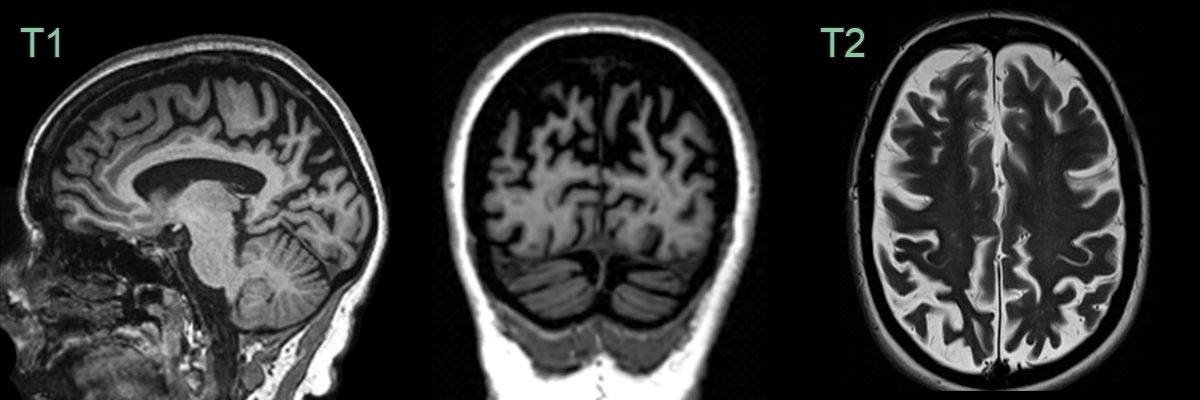

• A 60-year-old patient presented with logopenic aphasia and memory impairment.

• MRI showed marked widening of parietal and, to a lesser extent, occipital sulci.

• Hippocampal volume loss was less pronounced (MTAS 2).

• CSF biomarkers were consistent with Alzheimer's disease.